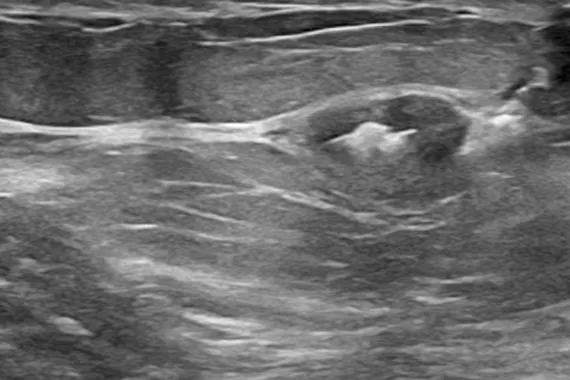

Marcadores de biopsia SecurMark®

Concebido para se mover o mínimo possível2, este marcador é altamente visível através de ultrassom após a sua colocação e continua altamente visível 6 semanas após a biopsia, o que é fundamental caso sejam necessárias intervenções futuras na mama.3 O marcador é composto por duas peças: um marcador permanente e uma malha bioabsorvível semelhante a sutura.

afirmam que a visibilidade por ultrassom foi boa a excelente após a colocação1

dos marcadores foram colocados com precisão na área prevista1

concordaram que o dispositivo é fácil de utilizar1